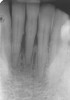

Figure 9  The 4-year postoperative radiograph.

Figure 9

This patient has been followed for 4 years with no complications and no discernable clinical changes in soft- or hard-tissue levels.